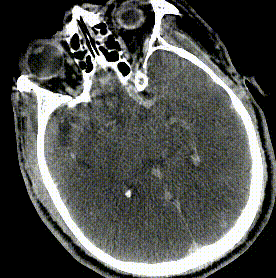

CT良好

“天又亮了”

局麻手术,术后密切观察下第二天头颅CT复查。

●术中替罗非班7ml静推,7ml/h微泵维持。

●20h后(拜阿司匹林、氯吡格雷负荷量重叠替罗非班4小时)。

●拜阿司匹林 0.1 qm

●氯吡格雷 75mg qm

●阿托伐他汀 40mg qn

●神清,言语含糊,左侧肢体肌力Ⅴ级,右侧肢体肌力Ⅲ-Ⅳ级。

●NIHSS评分10分,MRS 4分。